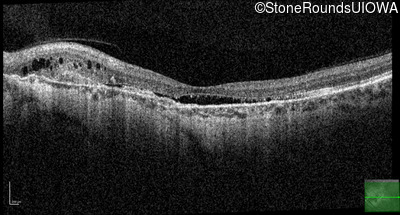

Age at visit: 58 years